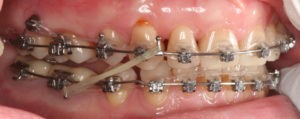

Для предварительной подготовки были привлечены пародонтолог и ортопед, поскольку отсутствие нескольких зубов, заболевание пародонта и дефекты твердых тканей зубов сопутствовали основной патологии. Проведены пародонтологические процедуры, вылечен кариес и его осложнения, изготовлены временные коронки для зубов с большим разрушением. На фото — временные коронки на боковых зубах.

Искривление окклюзионной кривой (плоскости смыкания зубов), возникшее в результате парадонтита, успешно удалось устранить, используя накусочные брекеты на верхних резцах и микроимплант, установленный во фронтальном участке нижней челюсти: